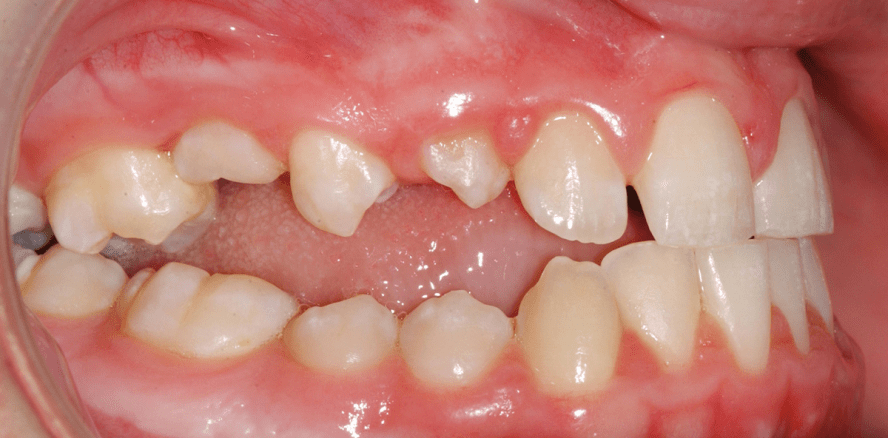

Das Ziel dieses Artikels ist die Erörterung der Ätiologie, der Behandlung und der Behandlungsstabilität posterior offener Bisse. Jay ist ein 15-jähriger männlicher Patient (Abbildung 1), der mit der folgenden vorrangigen Beschwerde bei uns vorstellig wurde: „Meine Backenzähne berühren sich nicht und deswegen fällt mir das Kauen sehr schwer.“ Die vorherige Krankengeschichte des Patienten war nicht beitragend, die bisherige Zahnkrankengeschichte war normal, seine Kiefergelenke asymptomatisch mit Übereinstimmung der zentrischen Relationsposition und zentrischen Okklusionsposition.

In der vertikalen Dimension stellten wir fest, dass Jays obere zentrale Schneidezähne in Okklusion und der distale Anteil der oberen ersten Molaren in Okklusion standen,während seine oberen seitlichen Schneidezähne, Eckzähne, Prämolaren und die Mesialhöcker seiner ersten Molaren jedoch nicht in Okklusion waren. Auch wenn es auf der Frontalsicht erscheint, als hätte der Patient eine lange untere vordere Gesichtshöhe (Lower Anterior Facial Height, LAFH) (Abb. 1a, Weichteil-Glabella-Subnasal < Subnasal-Weichteil-Menton), scheint er in der Profilansicht (Abb. 1c) eine normale LAFH zu haben, und seine Lippen sind kompetent. Das Verhältnis seiner unteren skelettalen Gesichtshöhe zur Gesamtgesichtshöhe (ANS-Menton/Nasion-Menton) war ein wenig größer als normal (LAFH/TAFH = 57%), aber sein Unterkieferebenenwinkel war im Normalbereich (FMA = 27°; SNMP = 32°). Also war Jay insgesamt vertikal normal, jedoch wies er einen beidseitigen posterior offenen Biss auf.

- Interpositionelle Zungengewohnheiten: Wie bei (funktionellen) anterior offenen Bissen können interpositionelle Zungengewohnheiten die Eruption von Zähnen verhindern und posterior offene Bisse verursachen. Wenn Sie vermuten, dass ein Patient eine interpositionelle Zungengewohnheit hat (üblicherweise ein posterior offener Biss mit einer klassischen „Football“-Form, Abbildung 2a), fordern Sie ihn auf, seine Augen zu schließen und sich zu entspannen. Sprechen Sie während dieser Zeit kurz mit seinen Eltern oder Ihrer Zahnarzthelferin. Bitten Sie dann den Patienten, die Augen zu öffnen (um ihn abzulenken), während Sie schnell und sanft seine Lippen auseinanderziehen (Abbildung 2b). Wenn er eine interpositionelle Zungengewohnheit hat, sollten Sie diese beobachten können. Der Umstand, dass die linke und rechte Bissöffnung von Jay (Abbildungen 1g und 1i) eine klassische „Football“-Form haben, sollte Sie veranlassen, zu vermuten, dass eine interpositionelle Zungenhaltungsgewohnheit seine hinteren Zähne an der Eruption hindert.